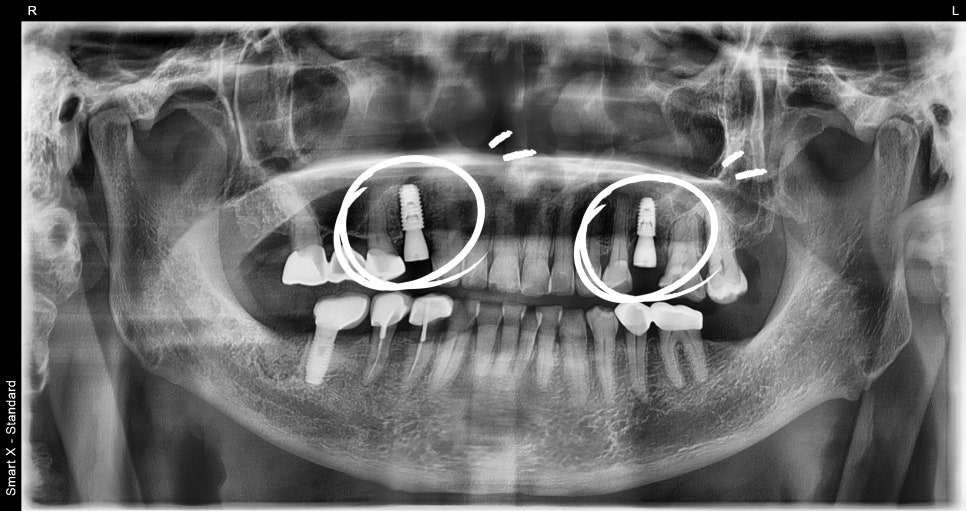

② 보험 임플란트 2개 식립

– 국소 마취 하에 하악 어금니 부위에 임플란트 2개를 식립했습니다.

– 수술 시간은 약 20분, 고령 환자분도 부담 없이 진행 가능한 방식입니다.

– 유착 확인 후 지대주 연결 → 최종 보철물 장착 → 교합 조정으로 마무리했습니다.